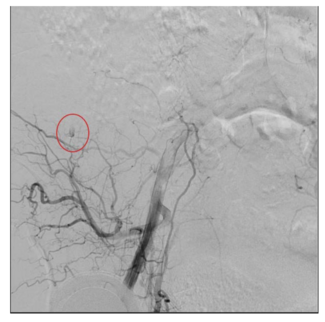

A 76-year-old female who developed sudden and severe left calf and foot pain after recent travel was found to have subtotal occlusion of the left popliteal artery and critical limb ischemia. Vascular access in the right CFA with a...